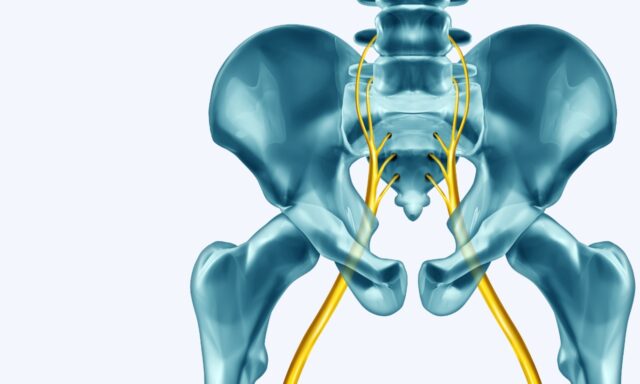

Lomber Radiküler Sendrom

Bu bölümde Adam Dobson ile birlikte lomber radiküler sendromun tanımından ciddi patolojilerin ekarte edilmesine ve radiküler sendromlu hastaları nasıl yöneteceğine kadar her şeyi konuşuyoruz. Ayrıca lomber radiküler sendromla ilgili kişisel deneyimlerini de paylaşıyor.